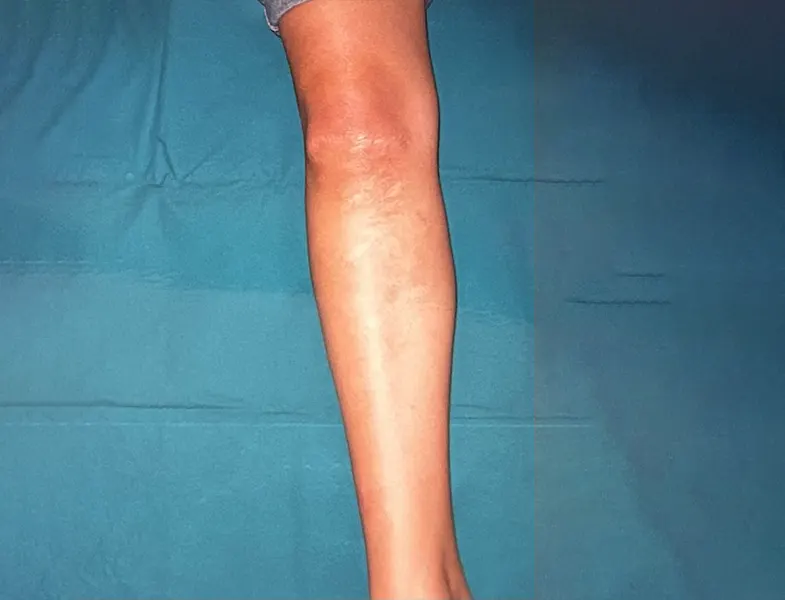

Φωτογραφίες Πριν και Μετά την Επέμβαση

Στην πρώτη υποενότητα, παρουσιάζονται συγκριτικές φωτογραφίες πριν και μετά την επέμβαση. Οι εικόνες αυτές αναδεικνύουν την εξέλιξη της κατάστασης του ασθενούς και την αποτελεσματικότητα των εφαρμοσμένων θεραπευτικών μεθόδων.